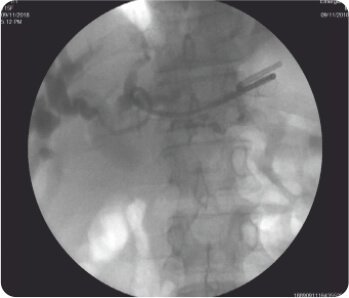

লিভারের দ্বিতীয় অংশে IHBRD এর EUS নির্দেশিত পাংচার পাকস্থলী থেকে করা হয়েছিল এবং কোলাঞ্জিওগ্রামের পরে, সিস্টোটোম ব্যবহার করে ট্র্যাক্টটি 10F পর্যন্ত ধারাবাহিকভাবে প্রসারিত করা হয়েছিল এবং পেট এবং লিভারের দ্বিতীয় অংশের সাথে সংযোগকারী একটি 60×10 মিমি সম্পূর্ণরূপে আবৃত বিলিয়ারি ধাতব স্টেন্ট স্থাপন করা হয়েছিল। ধাতব স্টেন্টের স্থানচ্যুতি রোধ করার জন্য ধাতব স্টেন্টের ভিতরে একটি 7F 7 সেমি ডাবল পিগটেল প্লাস্টিক স্টেন্ট স্থাপন করা হয়েছিল। কোনও পেরিপ্রোসিডেরাল জটিলতা ছিল না এবং বিলিরুবিনের স্বাভাবিকীকরণের পরে রোগীকে কেমোথেরাপি করা হয়েছিল। পদ্ধতির 3 মাস পরে ফলো-আপের সময়, রোগীর LFT স্বাভাবিক ছিল।

চোলাঞ্জিওগ্রাম